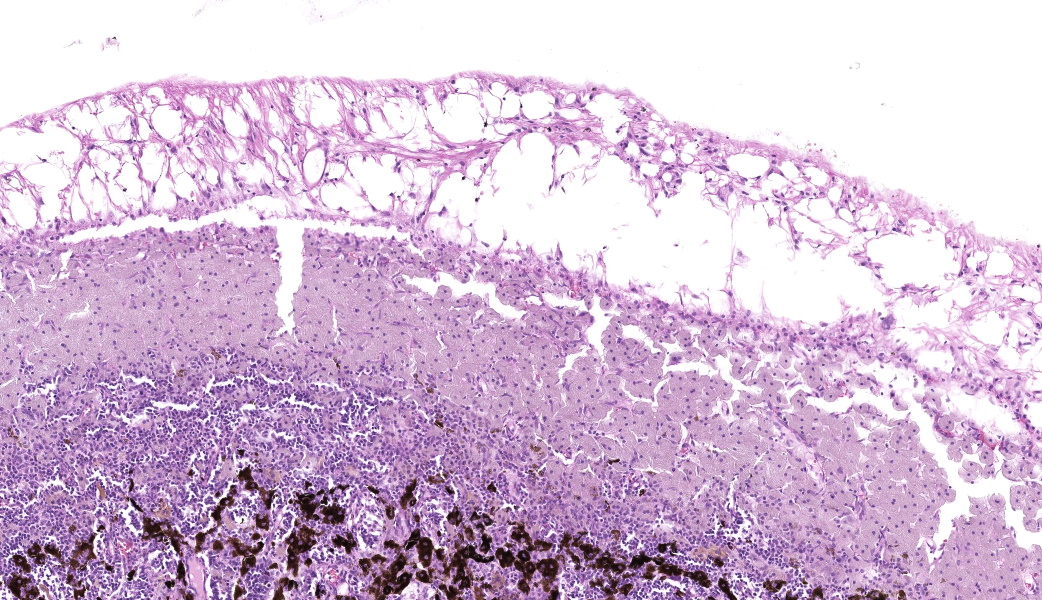

Expanding the anterior uvea, effacing the iris, and markedly expanding the suprachoroidal space is a densely cellular, unencapsulated neoplasm of neuroepithelial cells. Neoplastic cells are arranged in variably dense sheets and as palisading columnar cells surrounding a central lumen (Flexner-Wintersteiner rosettes) or surrounding eosinophilic fibrillar material (Homer-Wright rosettes) surrounded by collagenous and occasionally myxomatous stroma. Neoplastic cells are polygonal to fusiform, have a high nuclear to cytoplasmic ratio, and have distinct cell borders. The nuclei are round to ovoid, finely stippled, and have indistinct nucleoli. There are 16 mitoses in 10 high power fields and anisokaryosis is mild. The neoplastic cells are impinging upon the optic nerve, which has multifocal axonal degeneration and is infiltrated by a population of histiocytes, lymphocytes, and plasma cells, as well as scattered foci of hemorrhage. The retina has multifocal, disorderly components of viable photoreceptor and retinal ganglion cells, dense necrosis, glial scarring, and presumed Mueller cells. The retina is diffusely detached and lacks apparent retinal vessels. The retinal pigment epithelial cells have multifocally migrated through to the inner layers of the retina. The cortical lens fibers are moderately liquefied and homogenous and there is posterior migration of the lens epithelium, consistent with cataractous change. The corneal epithelium has marked, segmental ulceration and the outer corneal stroma in this area is mineralized with occasional breaks and is densely compact with fibrosis. Multifocally throughout the corneal stroma are areas of fibrosis, vascularization, and scattered neutrophils.Contributor's Morphologic Diagnoses:

Lastly, there was much discussion on the extensive secondary changes seen in this eye histologically, including keratitis and panuveitis. It is the opinion of conference participants that these changes were likely secondary to the medulloepithelioma and, as such, favored a traditional JPC morphologic diagnosis in such cases which is limited to the tumor and anatomic locations within the globe. This is not to say that the secondary changes are unimportant or should not be listed, but in true JPC tradition, changes secondary to a tumor are not included in the morphologic diagnosis.

Intraocular medulloepitheliomas arise from the primitive medullary epithelium of the inner layer of the optic cup. This structure normally develops into the retina, iris, and ciliary body epithelium. This neoplasm most commonly forms in the non-pigmented epithelium of the ciliary body but can rarely originate from the retina or optic nerve. In dogs and cats, intraocular medulloepitheliomas most often follow the playbook and arise from the ciliary body neuroepithelium, but in horses, they tend to go off-book and originate from the optic nerve head.7 Medulloepitheliomas are classified as either benign or malignant, and teratoid or non-teratoid. The teratoid form, as the name would imply, contains tissues that are not present within the normal eye (e.g., cartilage, bone, brain tissue, or muscle). In the conference case, due to the presence of primitive retinal tissue and neuropil within the neoplasm, conference participants favored a ?teratoid? classification for this neoplasm.